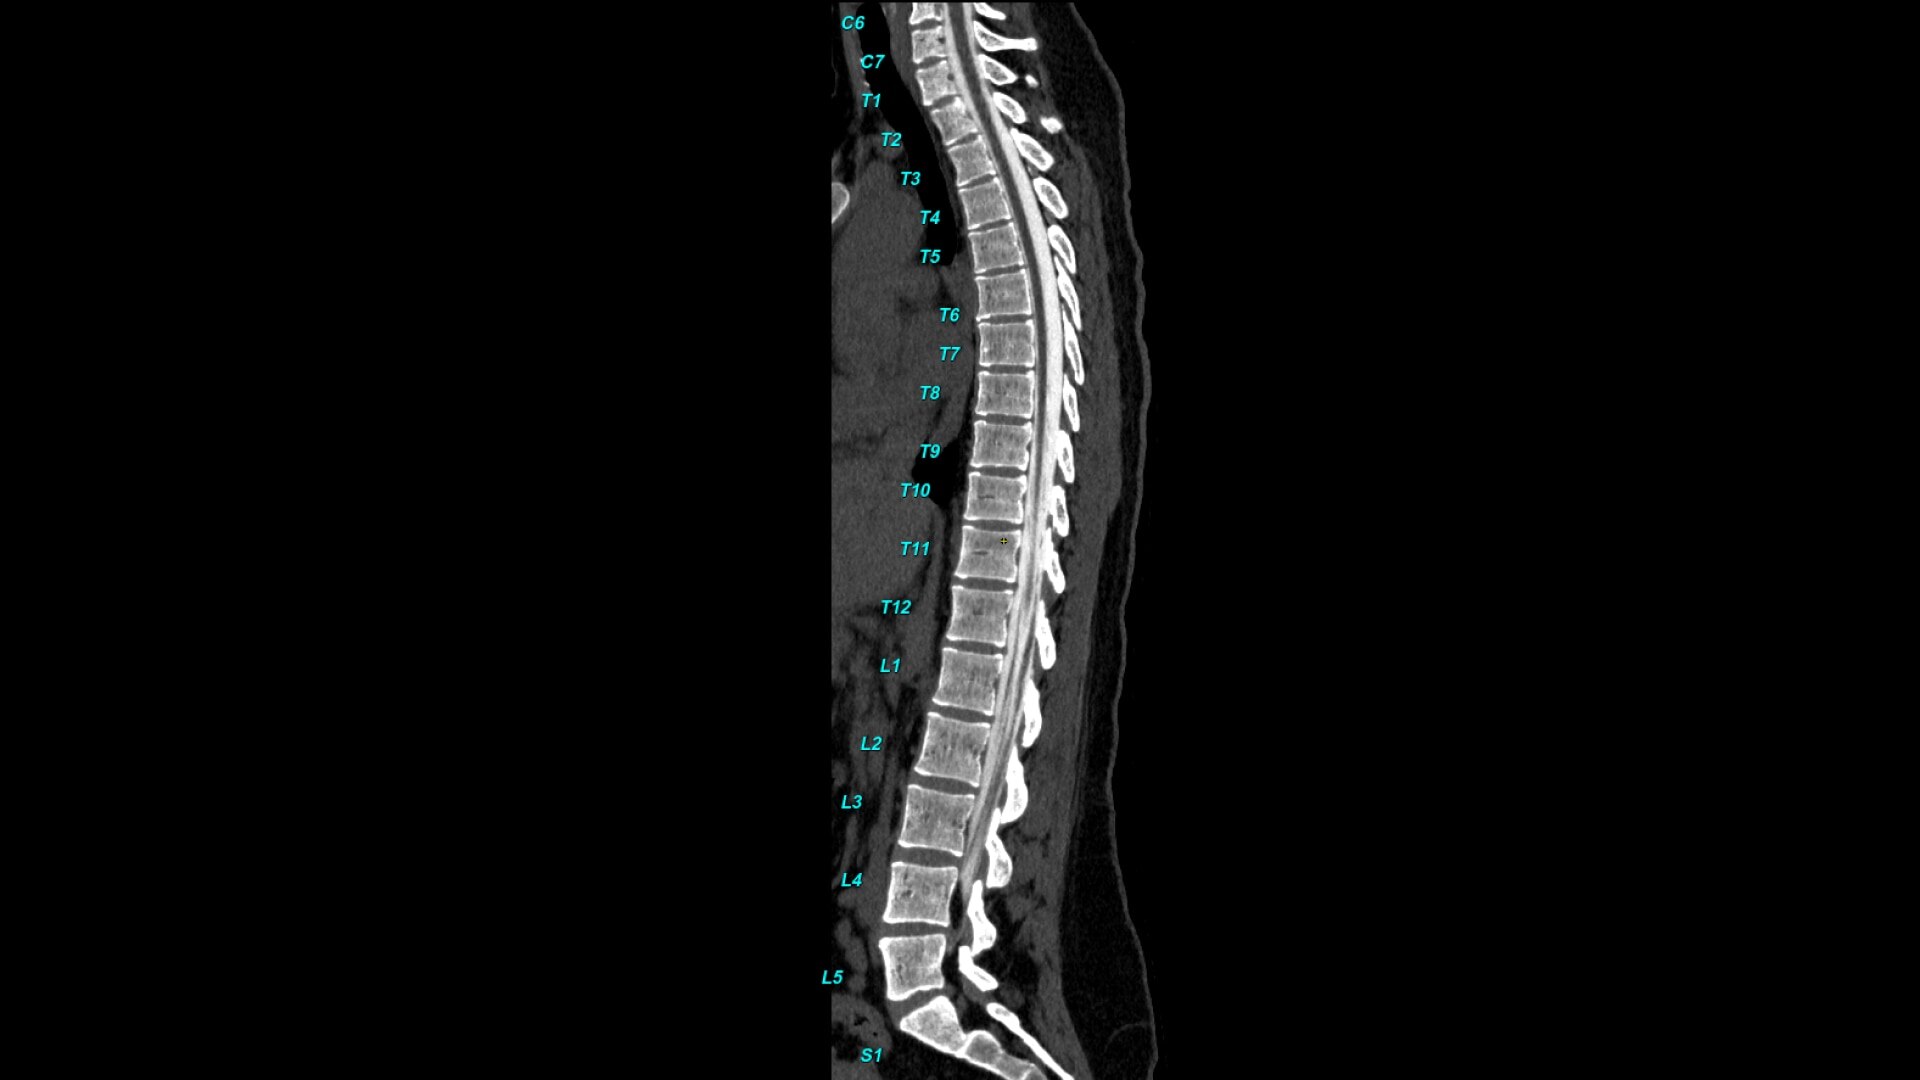

Bone VCAR

Spine assessment with deep-learning based CT application.

• Automated spine labeling

• Automated generation of a 3D trace to generate oblique and straightened reformat views

• Automated generation of oblique views perpendicular to vertebral bodies and disc spaces

• Works on full spine acquisitions as well as limited acquisitions containing segments of the spine